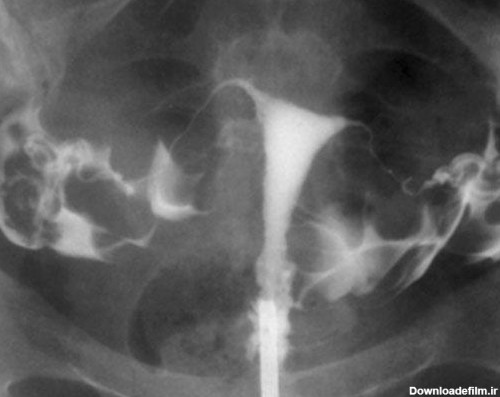

HSG یا عکس رنگی از رحم، یک تصویربرداری اشعه ایکس از رحم و لوله های فالوپ است. در این روش از نوع خاصی از اشعه ایکس به نام فلوروسکوپی و ماده حاجب استفاده می شود .

ازمشکلات رحم می توان به ناهنجاری ساختاری رحم که شامل بسته بودن لوله ها یا شکل ظاهری رحم اشاره کردبهترین روش بررسی مشکلات می توان از عکسبرداری رنگی رحم است